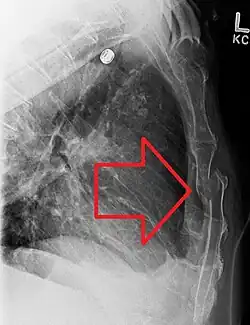

| A displaced sternal fracture as seen on plain X-ray | |

Diagnosis

X-rays of the chest are taken in people with chest trauma and symptoms of sternal fractures, and these may be followed by CT scanning.[13] Since X-rays taken from the front may miss the injury, they are taken from the side as well.[14]